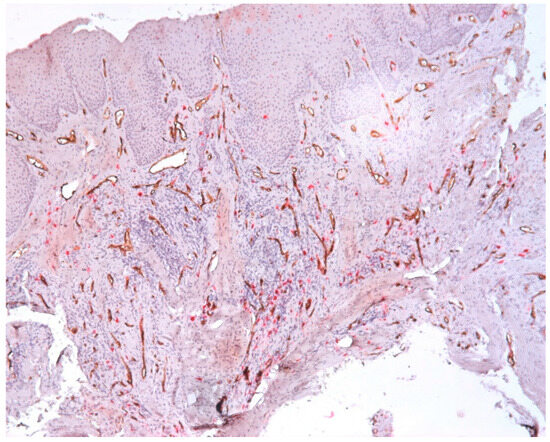

3.2. Mast Cells

3.3. Aspects of Microvessels

| Intraepithelial Mast Cells | Subepithelial Mast Cells | Connective Tissue Mast Cells |

|---|---|---|

| Mean (SD): 2.1 (1.9) | Mean (SD): 6.5 (4.8) | Mean (SD): 18.7 (7.7) |

| Range: 0.0–7.3 | Range: 0.0–13.7 | Range: 6.3–34.3 |